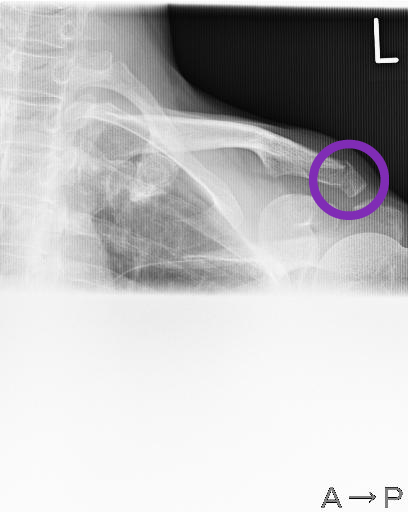

それではレントゲン撮りますね。ということでレントゲン技師の先生に導かれてレントゲン室に。2枚撮ったあとやはりマズいかも・・・という言葉があり、以前にも同じ所骨折しているのですよ。と話すと、その時の影が写っているかも知れないのでもう一枚撮りましょう。ということで再度別の角度から。

その後私の番となり、先生のところへ。「う~ん折れてるね。」

そしてこれ。

受診後。先生にブログやFBに掲載したいからiPhoneで写真撮っていいですか?と言うとどこが分かりやすいかな?と言って角度を変えてそして、それならCDにデータにした方がよいだろ。と言ってわざわざCDにして頂きました。最近のテクノロジーは(笑)